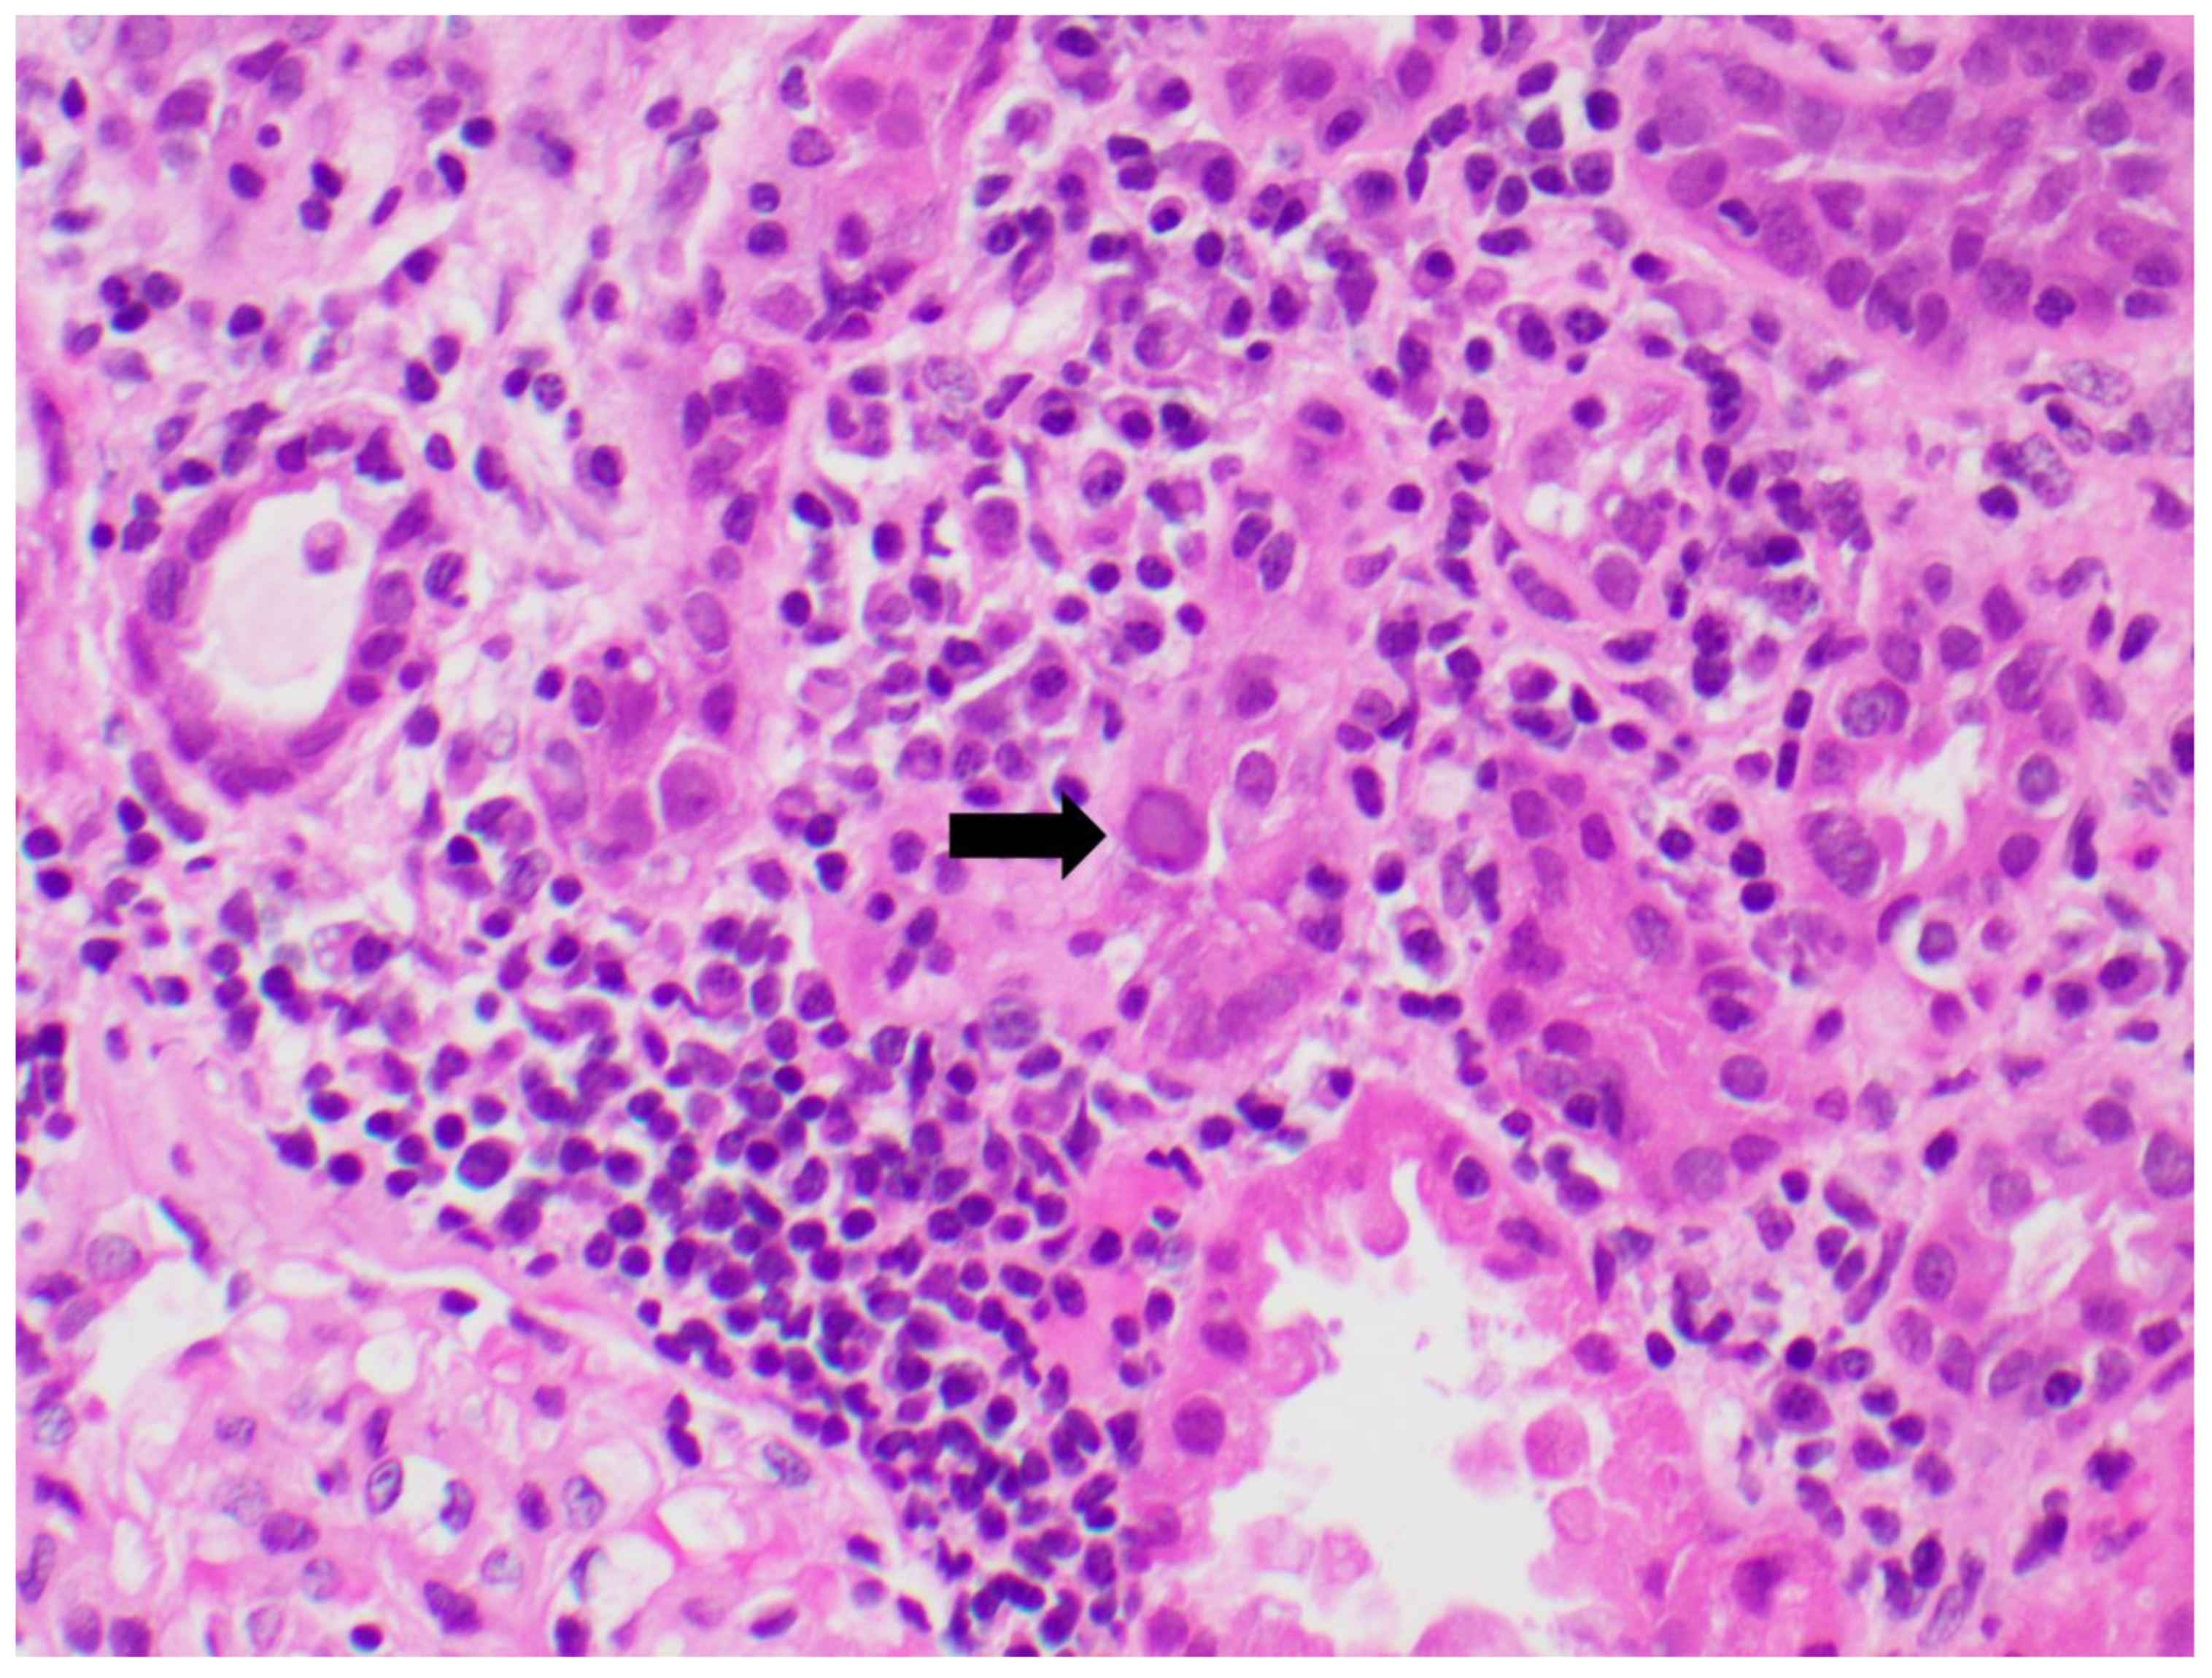

7.6. Histology

- Nickeleit, V.; Singh, H.K.; Randhawa, P.; Drachenberg, C.B.; Bhatnagar, R.; Bracamonte, E.; Chang, A.; Chon, W.J.; Dadhania, D.; Davis, V.G.; et al. The Banff Working Group Classification of Definitive Polyomavirus Nephropathy: Morphologic Definitions and Clinical Correlations. J. Am. Soc. Nephrol. 2018, 29, 680–693. [Google Scholar] [CrossRef]